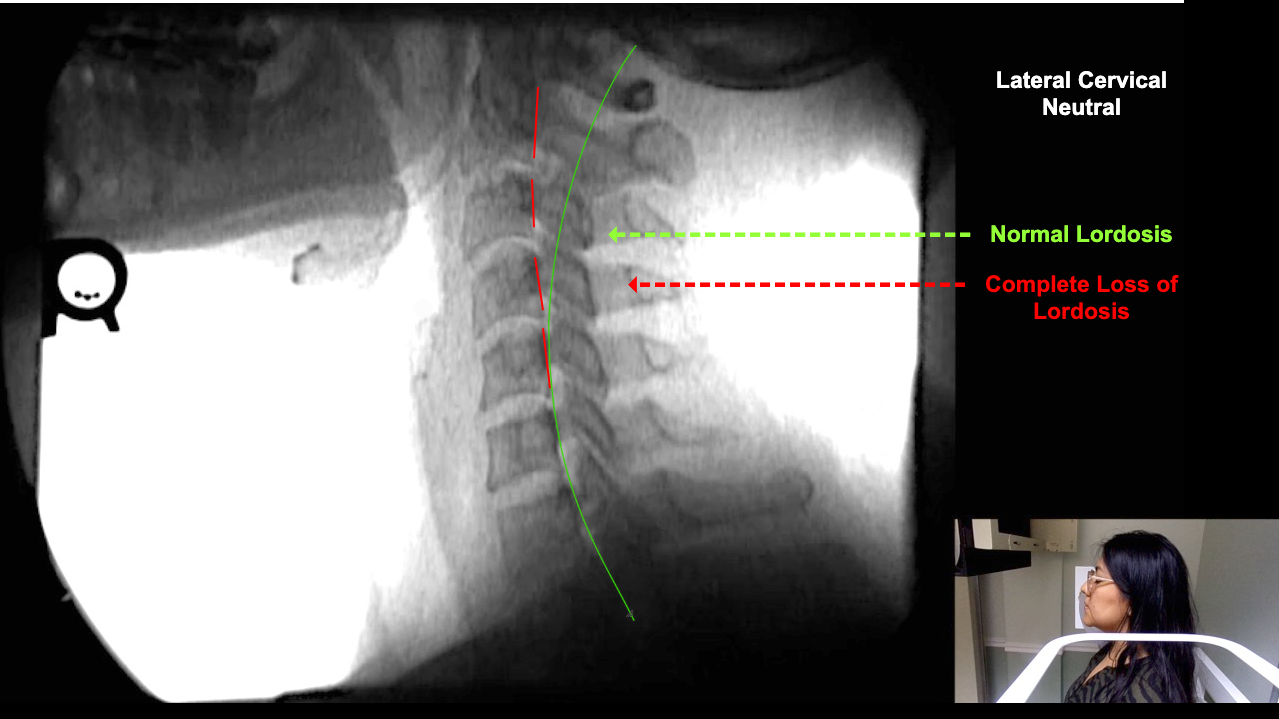

Home > Ana Cespedes